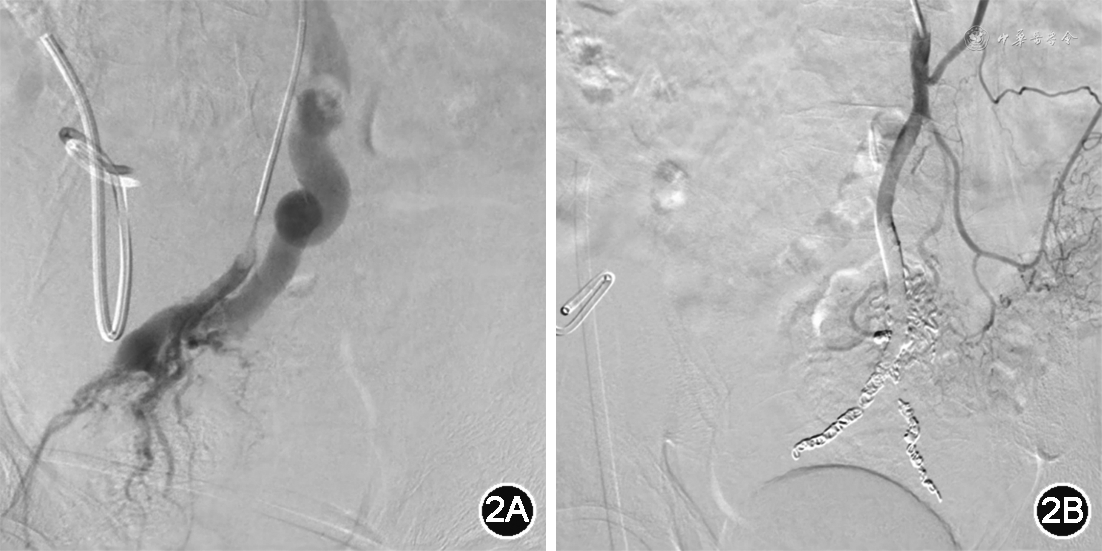

2021年11月20日患者转入介入治疗科行肠系膜下动脉造影及栓塞术。造影见肠系膜下动脉略增粗,肠系膜下静脉提前显示且明显增粗、局部见紊乱血管网,证实存在肠系膜下动静脉瘘(图2A)。为缓解门静脉高压、避免再次消化道出血风险,分2次分别超选左侧直肠上动脉、右侧直肠上动脉使用弹簧圈进行栓塞,应用组织胶与碘油(1︰5)适量予以巩固栓塞,复查造影,局部紊乱血管及肠系膜下静脉显影消失(图2B)。患者未出现消化道出血,腹水量减少、病情好转后出院。